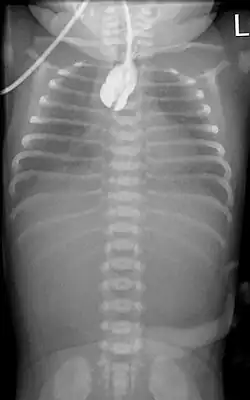

Zur Diagnosefindung wird die Speiseröhre sondiert. Ein federnder Stopp ist hinweisend. Eine Röntgenaufnahme des Brustkorbes zeigt die Luftfüllung des oberen Blindsackes (sog. Medaillonzeichen), und gegebenenfalls eine Luftfüllung des Darmes als Hinweis auf eine untere Fistel. Nur in Ausnahmefällen wird zusätzlich wasserlösliches Kontrastmittel gegeben.